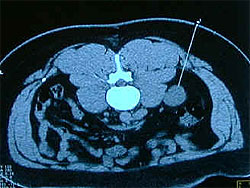

Проводять премедикацію. Місце укола голки обирають під час багатоосьові рентгеноскопії, керуючись наступним правилом: відстань від патологічного вогнища до місця укола має бути найкоротшою, а напрямок голки - перпендикулярним до поверхні грудної стінки. Знайдену точку фіксують на шкірі металевою міткою за допомогою лейкопластиру. Щоб уникнути забору некротизованої тканини, що знаходиться часто в центрі кулястого утворення, при великих пухлинах мітку ставлять ближче до одного з її країв. Хворого в положенні лежачи з трохи піднятим ногами (профілактика повітряної емболії!) вкладають на трохоскопі на спину (на живіт або на бік, залежно від зручності підходу до утворення в легенях). Під місцевою анестезією і під контролем рентгентелебачення до патологічного вогнища, або просто до легеневої тканини підводять голку, за допомогою якої отримують аспірат або біоптат.

Таким чином, голкова біопсія показана при кулястих тінях в плащевій зоні (якщо спіткала невдача при ендобронхіальній бронхофіброскопічній біопсії) і пухлинах заднього середостіння, недоступних для розширеної медіастіноскопії.